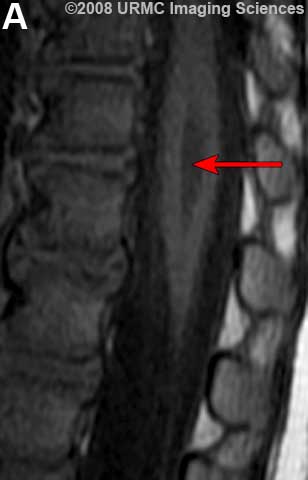

Желудочек терминальный (ventriculus terminalis, PNA, BNA, JNA; син. Краузе желудочек) — расширение в концевом отрезке центрального канала спинного мозга, расположенное в мозговом конусе вблизи от задней его стенки.

Желудочек терминальный

МРТ.  Терминальный желудочек

http://www.radsource.us/clinic/0807